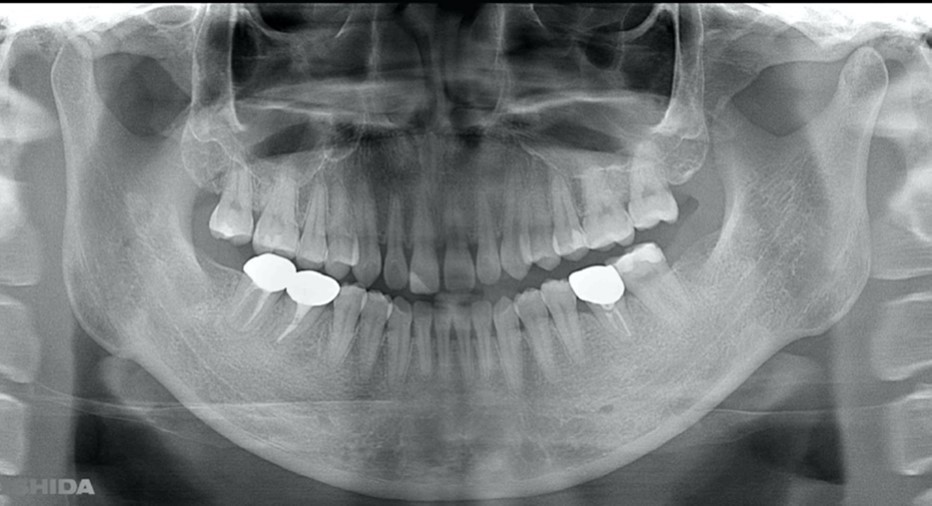

A 27-year-old female patient came to us with discomfort in the right lower jaw (Figure 1). Her primary symptoms were pain in the lower right tooth when biting and discomfort associated with not being able to chew well with the lower left single denture. The patient was married and had one young child, and previously received dental treatment in China, then had returned to Japan for childbirth and early childcare. The patient was a nonsmoker with moderate plaque control and medical history taking revealed no problems. In clinical and radiographic examinations, a root fracture was observed on tooth #46, which had been endodontic ally treated and restored with a full-cast metal crown. Periodontal probing revealed a pocket depth of 8 mm on the buccal center side of the tooth. No pain was detected with percussion and mobility of the tooth was normal. (Figure 1, Figure 2, Figure 3).

Figure 1.Clinical case of right auto transplantation. Panoramic view at initial examination.Tooth #46 was shown to be half decayed and a cystic lesion was found in the mesial root apex. Tooth #36 was lost, while #48 and #38 were present. There was a total of 29 teeth in the oral cavity.

Figure 2.Pre-treatment X-ray findings. A cystic lesion was found in the mesial and distal roots apex, and root nodule of #46.